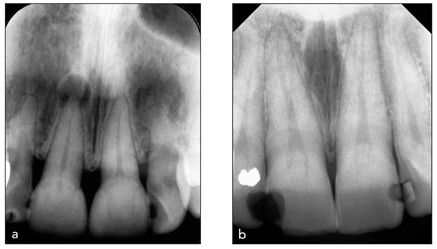

Hình 20-3 Phim X-quang các ví dụ về giải phẫu ống tủy “đơn giản”. Mặc dù luôn luôn có khả năng có thêm ống tủy hoặc điểm cong kín đáo, nhưng ống tủy của răng cửa giữa thường dễ sửa soạn. (a) Hình răng cửa giữa phải hàm trên có tổn thương quanh chóp. (b) Có phục hồi sâu ở cả hai răng cửa giữa hàm trên.